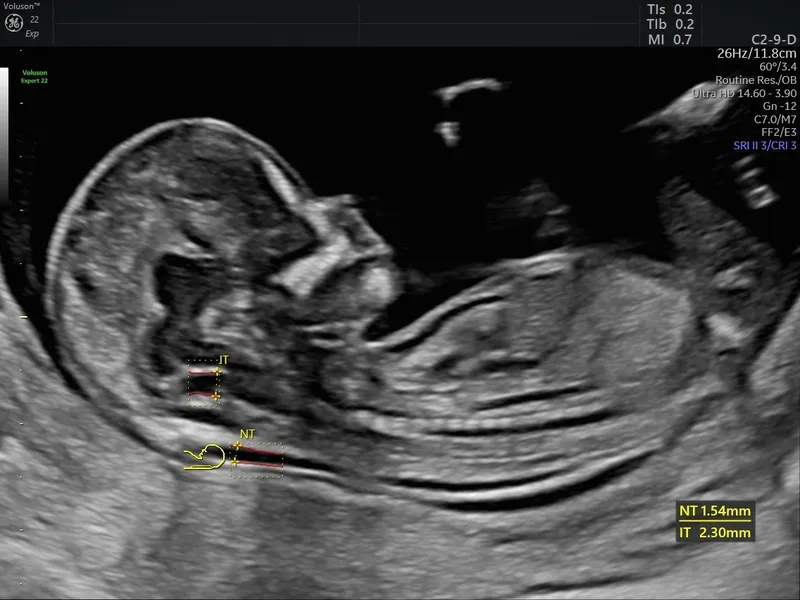

- Sonographic Markers (NT Scan):

- ↑ Nuchal Translucency (NT)

- Nuchal Translucency (NT) is the most important first-trimester ultrasound marker for Down syndrome.